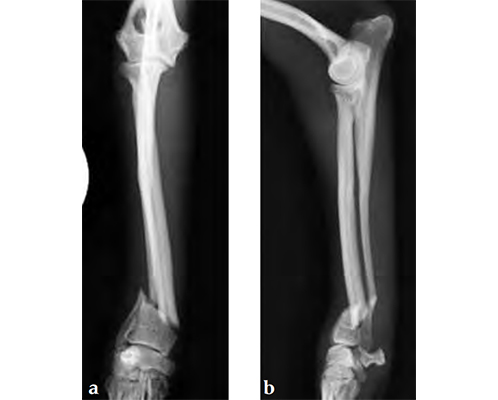

A 1-year-old female Yorkshire Terrier (1.7 kg) fractured the right distal radius and ulna (similar to a Colles fracture in humans). Open reduction and internal fixation was performed using a 7-hole 2.0 mm VET LCP notched head T-plate (a 7-hole plate was cut to eliminate the proximal two combination holes). The fracture was reduced and the distal bone fragment secured with two locking screws; the notch in the T-plate allowed independent contouring of this portion of the plate adjacent to the articulation. Compression was then applied across the fracture by loading one screw (second screw-hole proximal to the fracture); a second standard screw was then secured adjacent to the fracture (angled away/proximal to the fracture). The remaining screws were placed in a locked fashion. Despite the attempt at anatomical reduction, a slight (~1 mm) step was observed in the craniocaudal reduction (Fig 3). No fixation was applied to the ulna. A soft, padded bandage was applied to the forelimb (distal to the elbow joint) for minimal support and to control swelling.